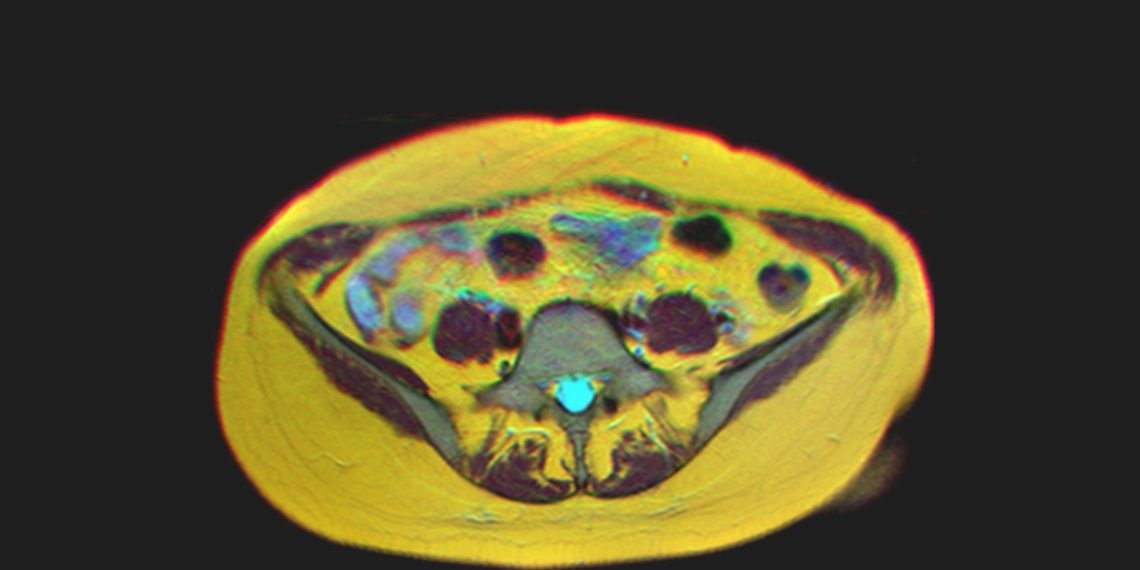

Diagnosis and Medical Imaging of Adenomyosis